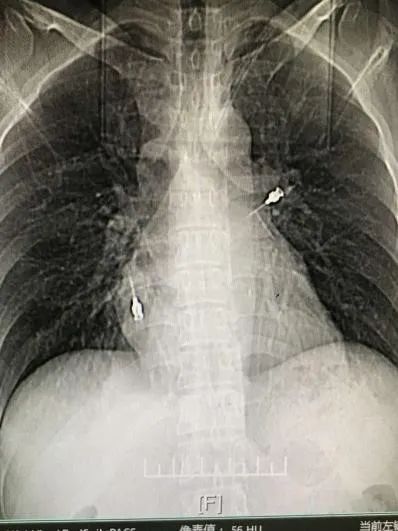

章医生:“你的胸部ct我看了下,是虾呛到气管里了,要马上在气管镜下取出来。”

(ct结果显示王先生的左肺有一只虾)